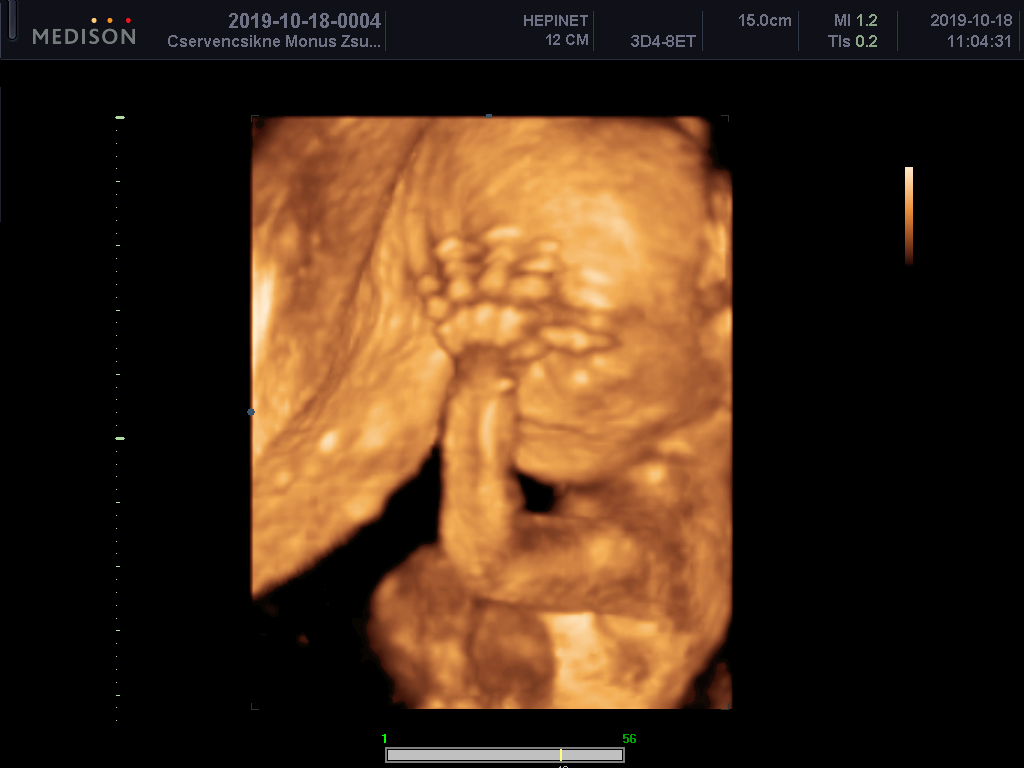

21. hét 4D ultrahang

Ti most tényleg engem vizsgáltok?